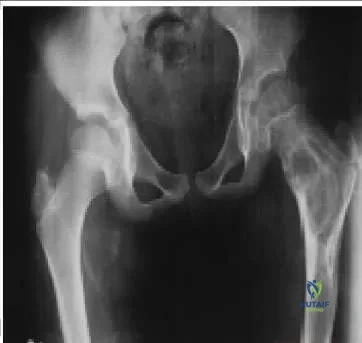

A 10-year-old child, who has no history of fever, trauma, or infection, presents with minimal pain and a Trendelenburg gait on the left (Slide). Which of the following is the most likely diagnosis:

This patient has fibrous dysplasia. The diffuse nature of the changes over a long portion of the bone, which includes blurring and thinning of the cortex, are classic signs of the disorder.